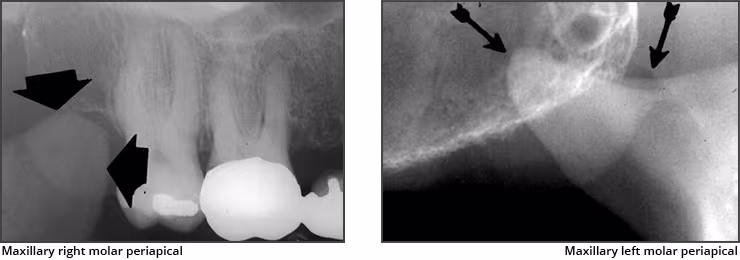

Coronoid process – The coronoid process of the mandible is the triangular bony portion of the anterosuperior aspect of the ramus. This mandibular structure can be recorded on maxillary molar periapical images as the ramus moves forward when the patient’s mouth is open. It appears as a bilateral triangular or thumb-like radiopacity on posterior maxillary images. The triangular portion projects forward toward the midline. The coronoid process is the only mandibular structure recorded on maxillary molar periapical images.

Maxillary tuberosity – The maxillary tuberosity is the rounded end of the alveolar process of the maxilla. This radiopaque structure appears bilaterally on maxillary molar periapical images and often on maxillary premolar periapical images and molar bitewings. The tuberosity curves upward at the end of the maxillary alveolar process. The tuberosity gives a smile appearance to the maxilla and the dentition particularly on bitewings.